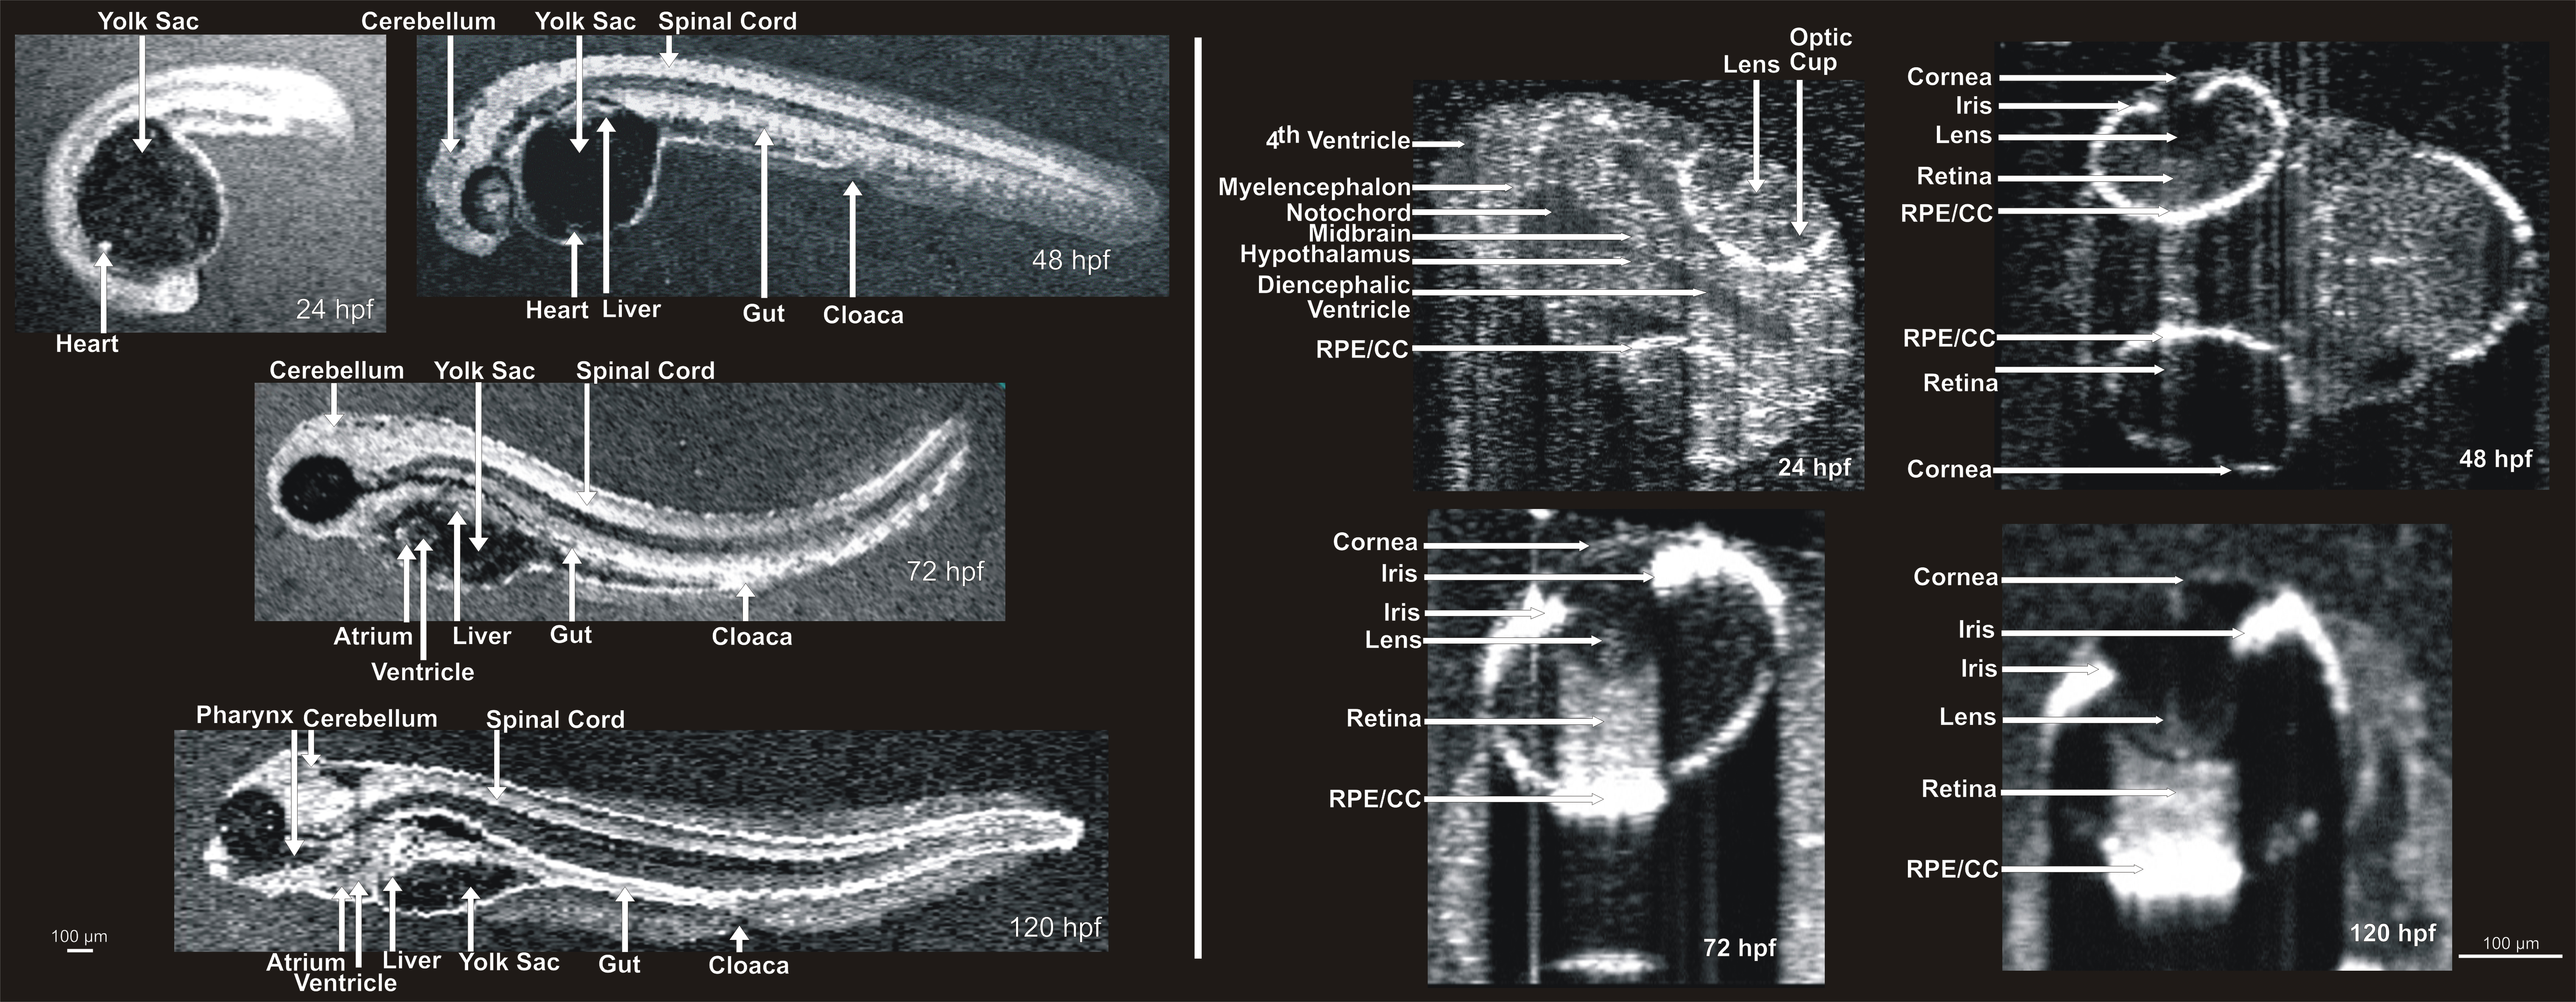

Figure 6. Visualization of developing

internal anatomy of zebrafish embryos. Twenty-four hours post

fertilization (hpf): A C-mode slice (left, 750 μm) centered on the eye,

and a repeated line scan (right, 750 μm) centered on the brain and eye

provide visualization of numerous internal structures within the brain,

eye, and gut, as well as fluid spaces developing as ventricles within

the brain. 48 hpf: C-mode slices at the level of the ear (left, 750 μm)

and notochord (right, 1.5 mm). Microscopic structures of the eye,

brain, gut, and heart can be visualized throughout. Blood within

vessels and the heart create a bright reflection when isolated in a

sagittal plane (left) while casting shadows on underlying tissues

(right). 72 hpf: An averaged repeated line scan of the eye (left, 750

μm) reveals the cornea, lens, retina, and retinal pigment epithelial

and choriocapillaris complex (RPE/CC) layer of the right eye of a

zebrafish embryo. The RPE/CC of the left eye is the only structure

within the left eye with sufficient reflectance to be observed. The

C-mode slice (right, 1.5 mm) centered on the heart provides

visualization of both chambers of the heart as well as numerous

structures within the gut and brain. 120 hpf: An averaged repeated line

scan of the eye (left, 750 μm) shows the cornea, lens, retina, and

RPE/CC layer of the right eye. A C-mode slice (right, 4 mm) displays

structures of the heart, gut, and brain, documenting the development

that has occurred in only 120 hpf.